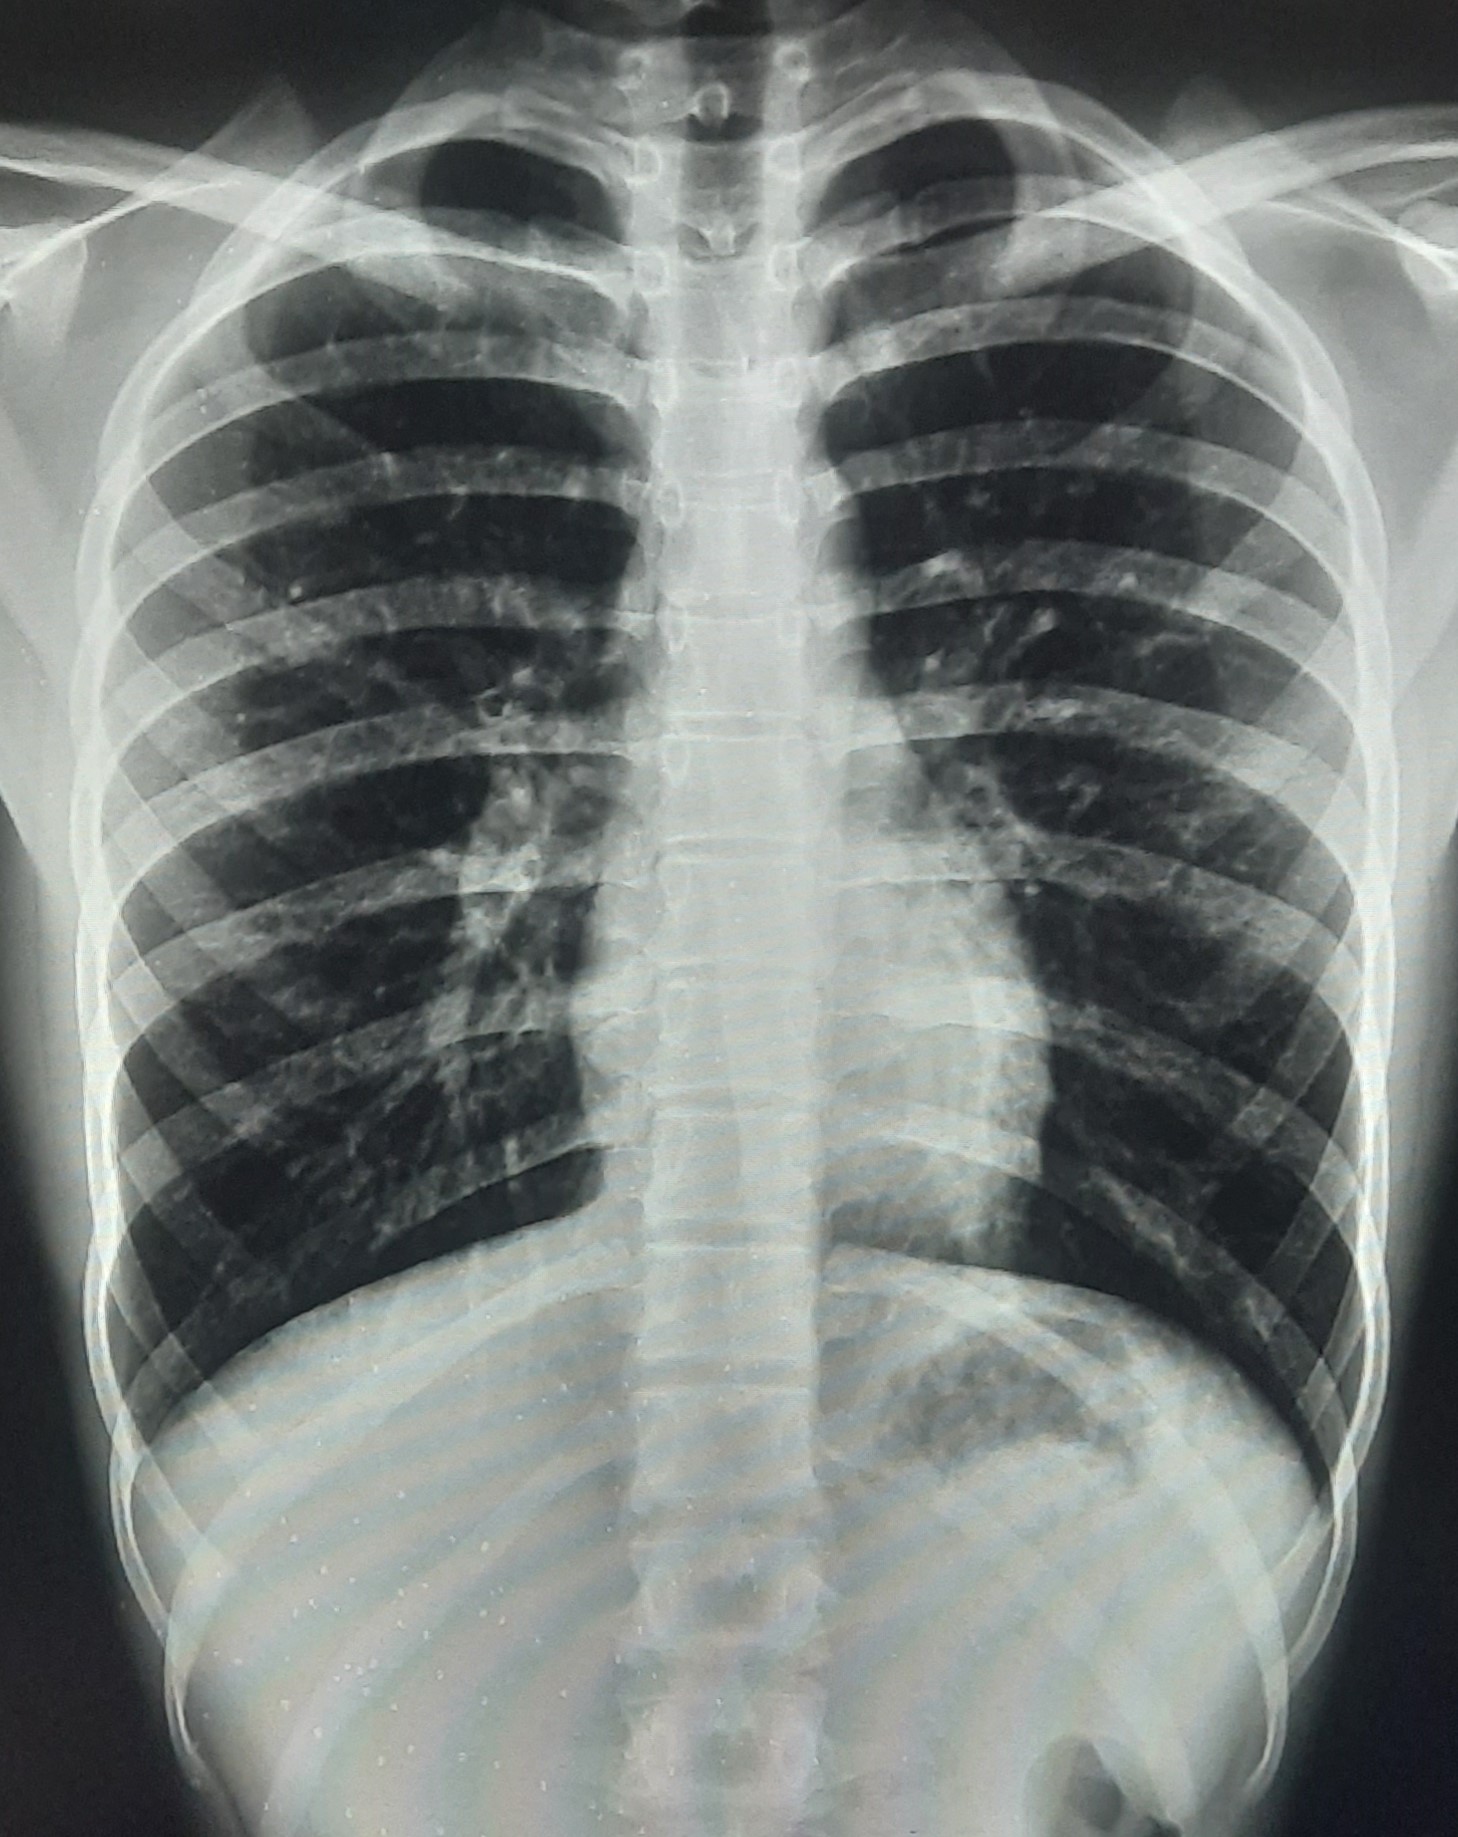

| 283 | IGGMC, Nagpur, Nagpur | P2 | 29-4189 Follow-up of 29-3923 |

Monali Pralhad Milmile | Consent taken on Paper | 46 Yrs. |

Provisional Diag : PTB Follow-up

Final Diag : Pleural Effusion |

TB Case (Confirmed) | Right Sided Upper Zone Fibrotic Lesion, Tracheal Pull Left side, Right sided & Left Sided Pleural Thickening Present, Right sided & Left Sided CP Angle Blunting Present, | Abnormality visible on x-ray |